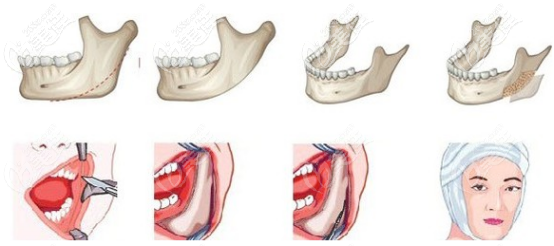

今天來(lái)回答“韓國(guó)雙顎手術(shù)和正頜手術(shù)有什么不同,和雙鄂手術(shù)適合哪些人做”兩個(gè)問(wèn)題。其實(shí)正頜手術(shù)和雙顎手術(shù)就是一個(gè)手術(shù),只是叫法不同罷了,國(guó)內(nèi)叫正頜,韓國(guó)叫雙顎,都是用來(lái)改善地包天。... b1700 G0 V0